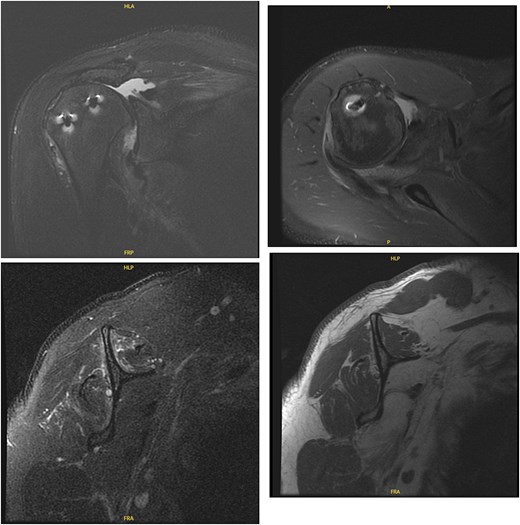

At 2-week follow-up, he reported continued shoulder pain. His right-sided paresthesias had resolved; however, he reported continued paresthesias into his left forearm and hand. He had significant bilateral limitation in range of motion, and weakness on internal and external rotation, more so on the left. Special tests included a positive Jobe test, drop arm test, belly press test, Obrien’s test, and Speed’s test bilaterally, as well as a positive left-sided bear hug test. He was advised to start gentle range of motion, avoid lifting, and was sent for bilateral shoulder MRIs (Figs 5 and 6).

MRI of the right shoulder demonstrating full-thickness tearing of the supraspinatus and infraspinatus with medial tendon retraction, a high riding humeral head, intermediate grade partial thickness tear of the teres minor, severe fatty atrophy of the subscapularis muscle belly, labral degeneration, and tearing, partial thickness tearing of the inferior glenohumeral ligament, anterior-inferior glenoid subchondral marrow edema, and severe glenohumeral cartilage abnormalities.

MRI of the left shoulder demonstrating a full-thickness tear of the supraspinatus and infraspinatus with tendon retraction, high grade partial thickness tearing of the subscapularis, full-thickness tear of the biceps long head tendon, complex anterior labrum tear, partial thickness tear of the inferior glenohumeral ligament including the anterior and posterior bands, inferior glenoid subchondral marrow edema, and moderate glenohumeral degenerative changes.